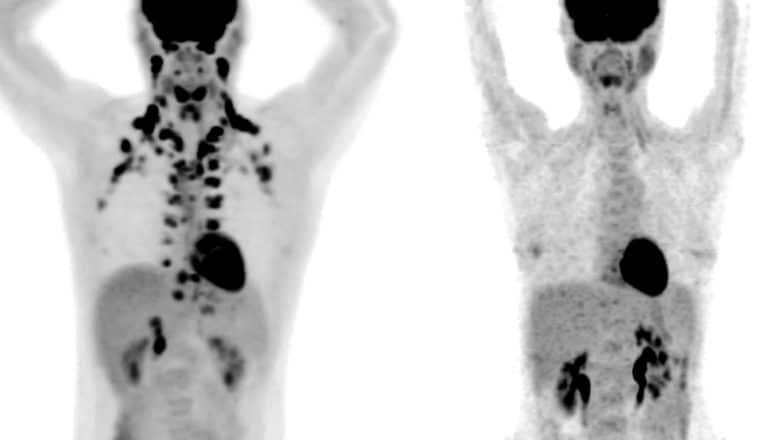

Two PET scans of people side by side

Large-scale studies, however, have practically proved impossible because the tissue shows up only on PET scans, a special type of medical imaging.